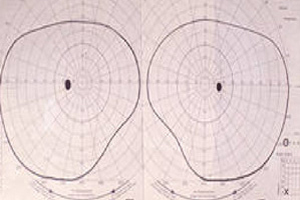

Die Bestimmung des Gesichtsfeldes dient dazu, das Ausmaß eines eventuell bereits bestehenden Schadens festzustellen. Diese Untersuchungen sind subjektive Verfahren, in denen es auf die Konzentration und Mitarbeit des Patienten ankommt. Häufigere Gesichtsfeldmessungen führen zu einer besseren Verlaufskontrolle.

Kinetische Perimetrie (Goldmann)

Ein definierter Lichtreiz (heller Punkt) wird von außen kommend zur Mitte geführt bis der Patient ihn bemerkt und dann registriert. Dabei schaut der Patient in eine Halbkugel.

Goldmann-Perimeter

manuelle Aufzeichnung - normales Gesichtsfeld

Statische Perimetrie

Bei dieser Untersuchung schaut der Patient ebenfalls in eine Halbkugel. Ein Computer bietet ihm Lichtpunkte unterschiedlicher Größe und Helligkeit an, welche der Patient melden muss. Die Aufmerksamkeit wird ständig durch Fangfragen kontrolliert.

defektes Gesichtsfeld

Foto statische Perimetrie

Gesichtsfelduntersuchung